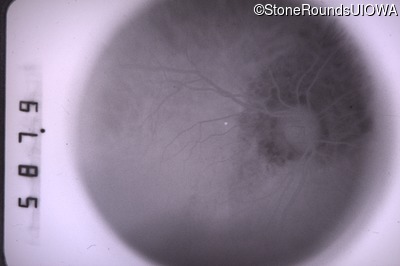

Fundus Photography - Right - 20/60 -2

Exemplar